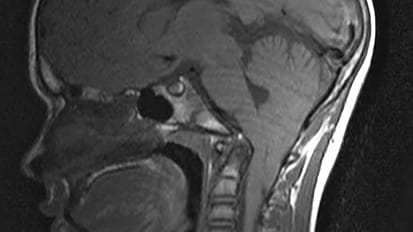

MRI scans of a patient’s brain showing the chronic active lesions (areas of localized damage marked by arrows within magnified insets) associated with multiple sclerosis (MS). Johns Hopkins Medicine and National Institute of Neurological ...